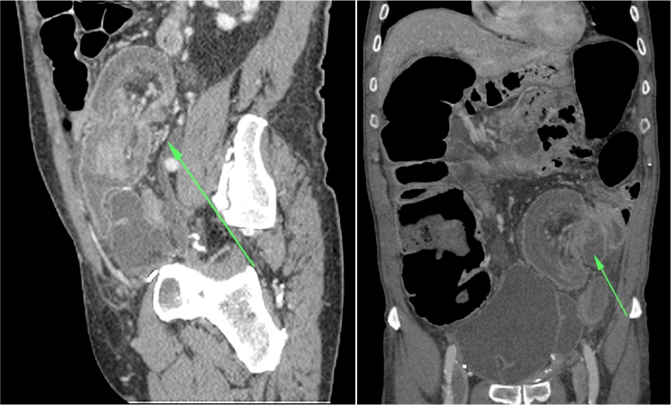

- El hallazgo patognomónico es el signo de la escarapela o diana identificable en la TC o ecografía.

- Podemos ver la imagen de «Intestino dentro de intestino” gracias a las reconstrucciones multiplanares.

Aunque el diagnóstico es sencillo, la TC es insuficiente para determinar la causa subyacente. Existen una serie de hallazgos que nos permiten caracterizar la invaginacion y valorar la gravedad, lo cual determina el tratamiento a seguir.

- Segmento largo (>4cm)

- Diámetro aumentado

- Obstrucción intestinal asociada

- Punto guía reconocible

- Localización en colon.